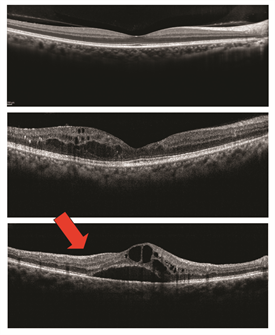

Fluorescein angiography (Figure 1) and optical coherence tomography (OCT; Figure 2) are 2 common tests to evaluate macular edema. Based on the appearance of fluid on these tests, macular edema may be widespread, localized, or be made up of many small blisters surrounding the center of the macula—a common form called cystoid macular edema.